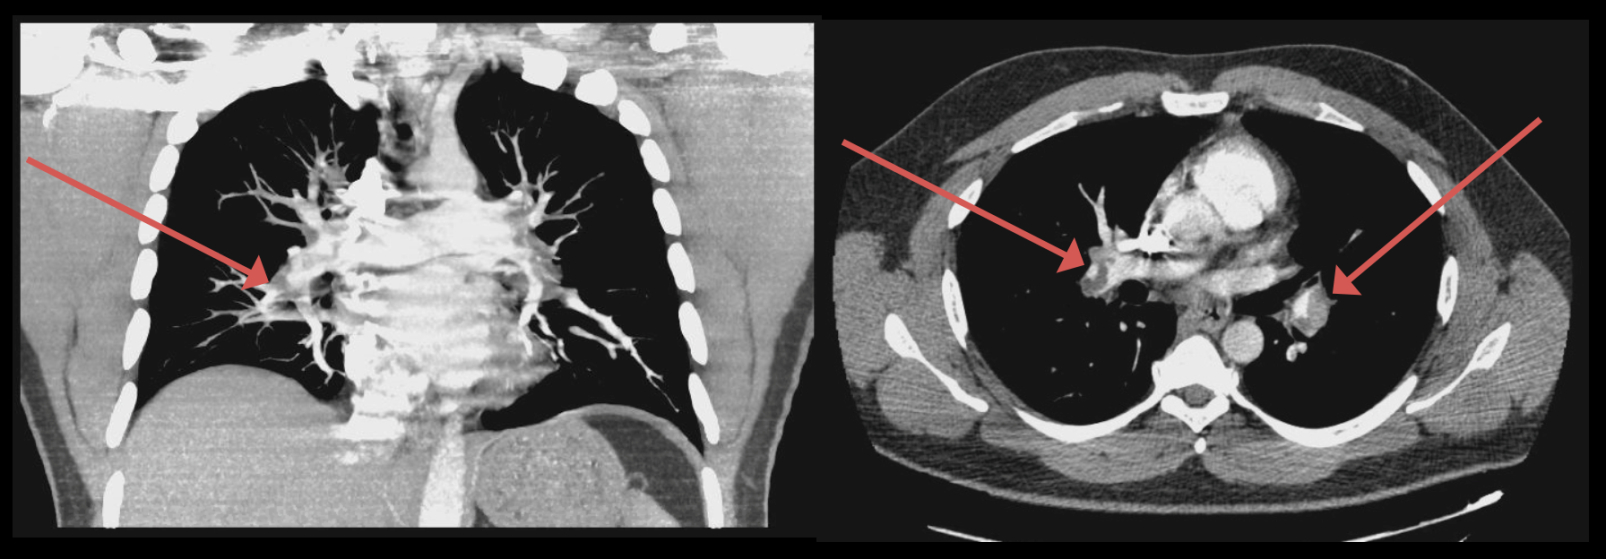

Computed tomography (CT) angiography of the chest showed extensive pulmonary emboli (PE) in the bilateral distal main, interlobar, and segmental pulmonary arteries of both lungs (Figure 1).

Figure 1. CT angiography showed bilateral pulmonary emboli (arrows).